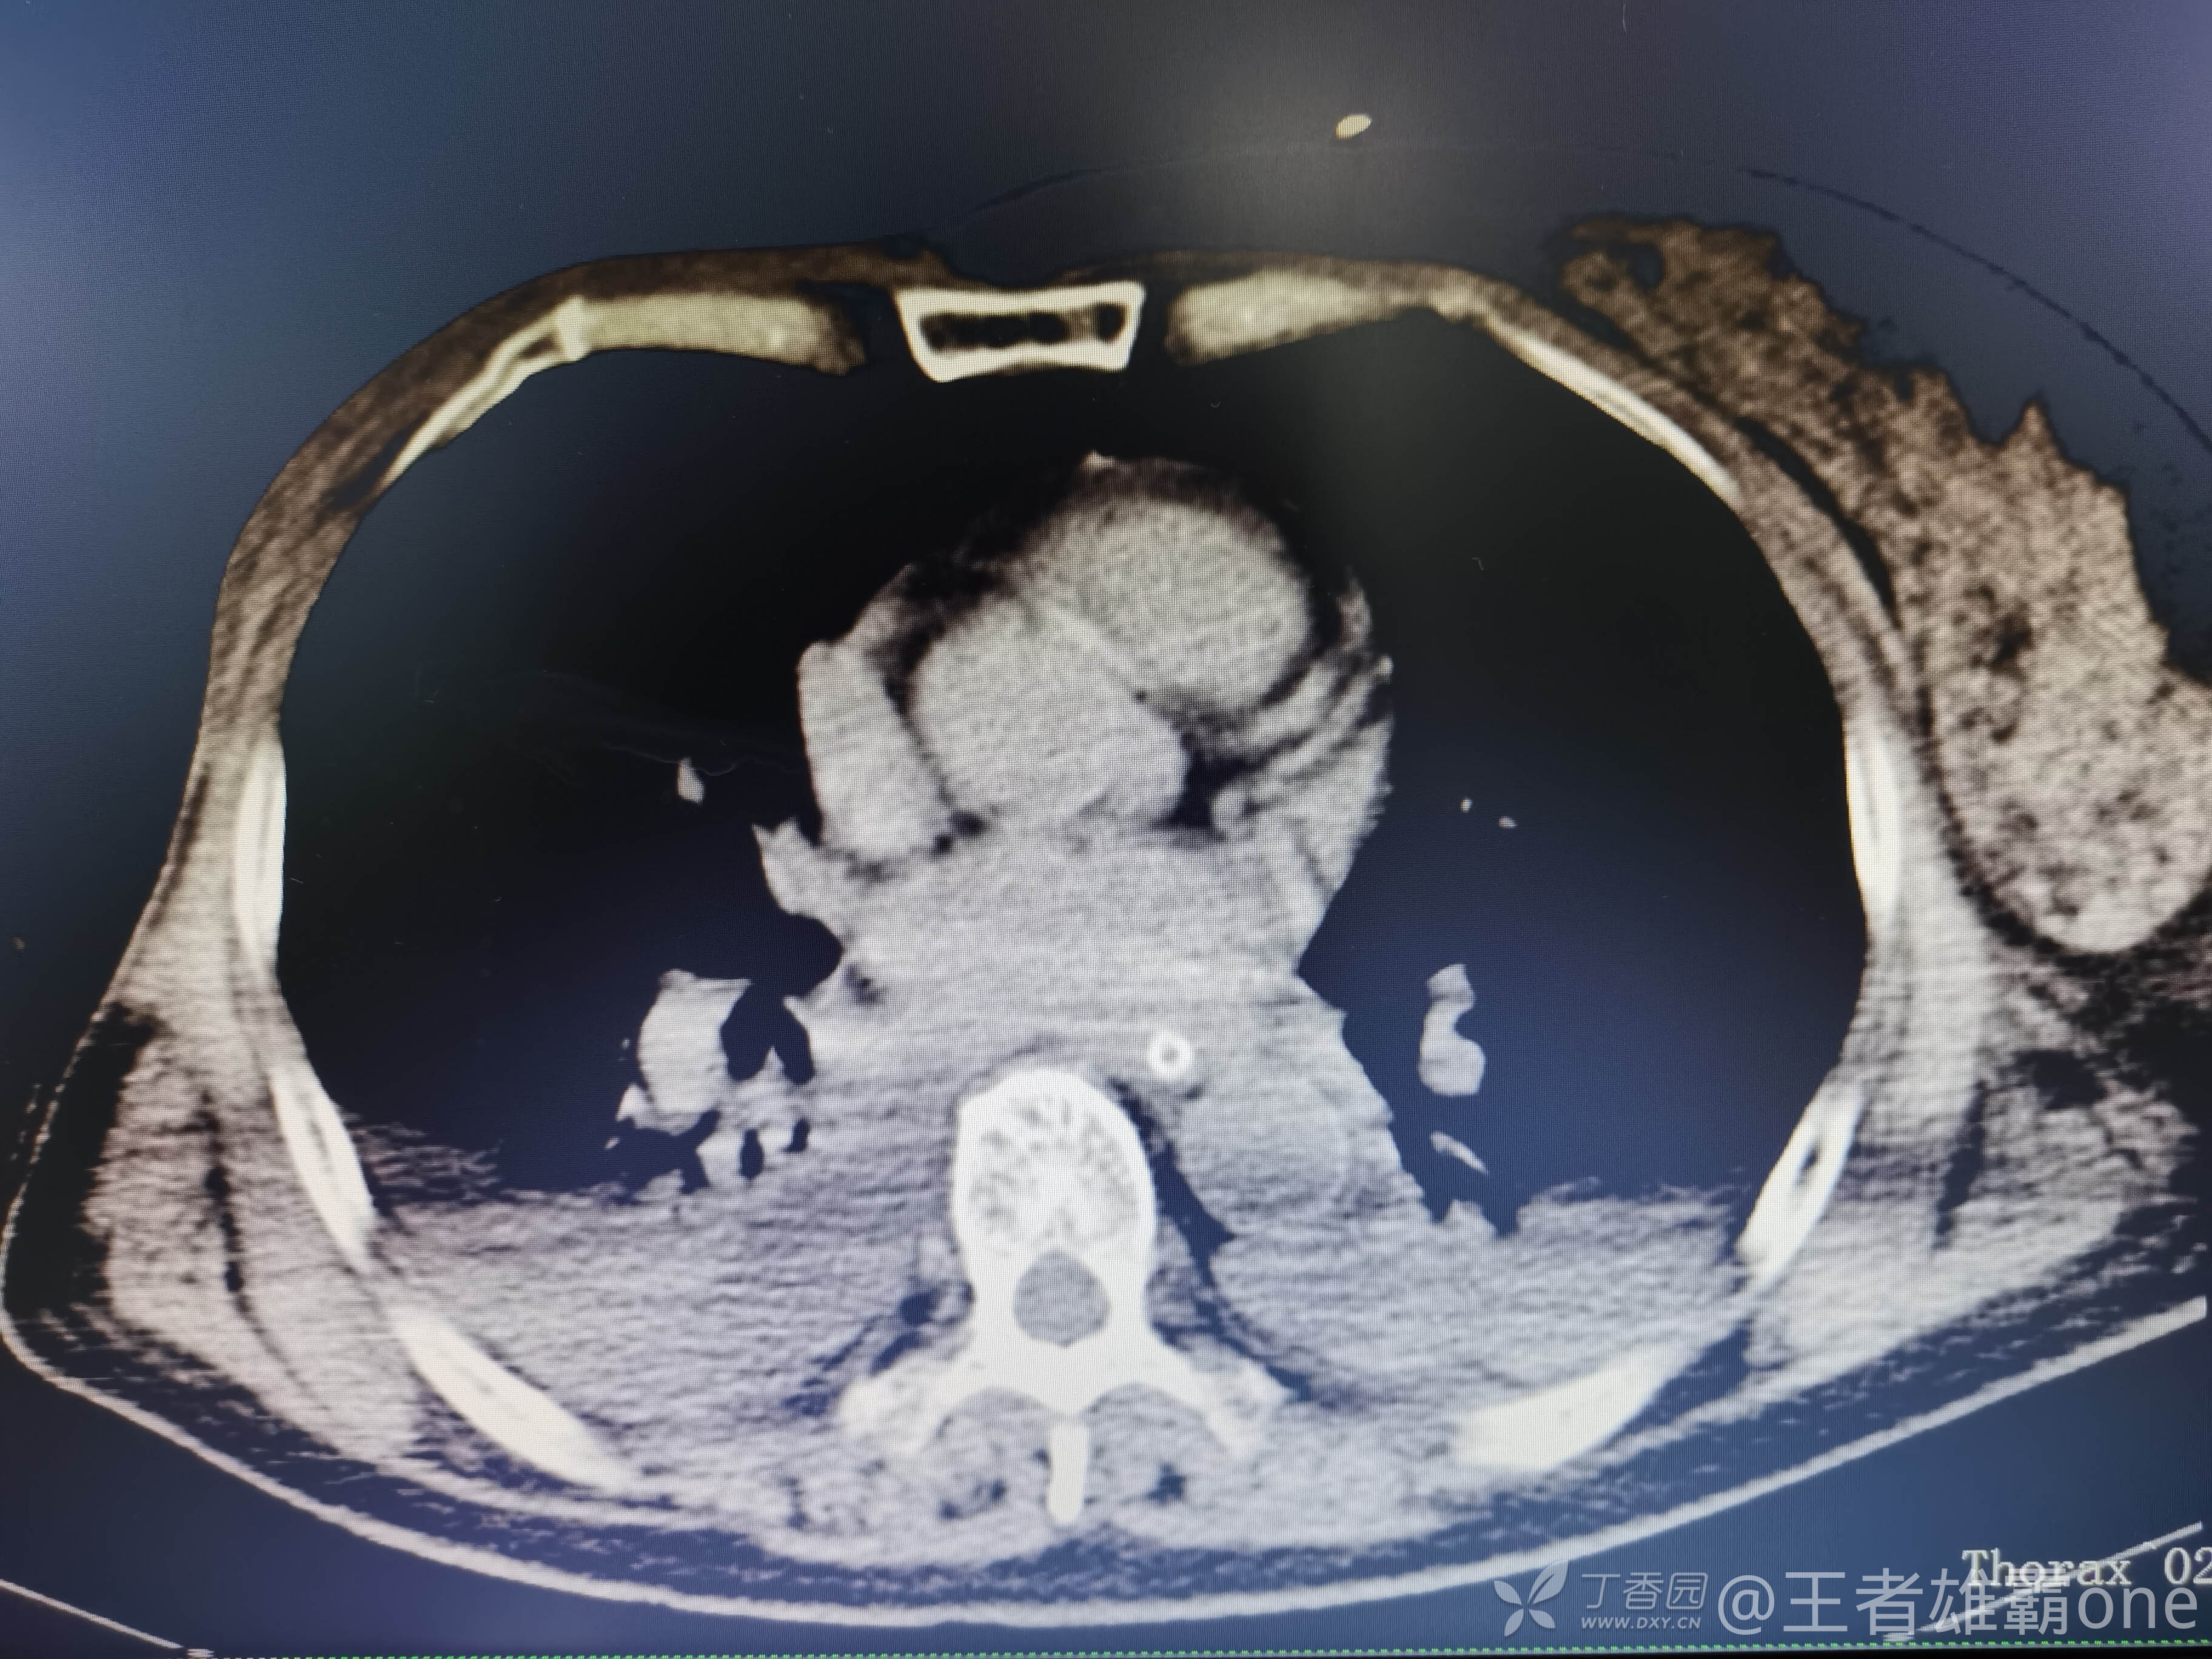

西门开心 推荐63岁女性,因车祸致短暂神志不清、多处疼痛4h入院。简单病史:伤后送至医院急诊就诊。完善头胸腹CT等检查,完善新冠核酸、血常规等化验。血常规提示血红蛋白62g/L。头颅CT提示未见明显外伤性改变。胸腹部CT视频见下:

早上复查血常规:血红蛋白100g/L,白细胞11.1×109/L,血小板29×109/L。凝血功能:APTT37.9s,纤维蛋白原3.01g/L,凝血酶时间18.6s,D二聚体21530ug/L。生化:白蛋白36.2g/L,胆红素指标正常,谷丙56U/L,总胆红素38mmol/L,直接胆红素12.1mmol/L,谷草57U/L,肌酐91.1ummol/L,尿素13.97mmol/L,超敏C反应蛋白142.1mg/L。降钙素原17.70ng/ml。脑钠肽前体2164pg/ml。复查胸部CT: